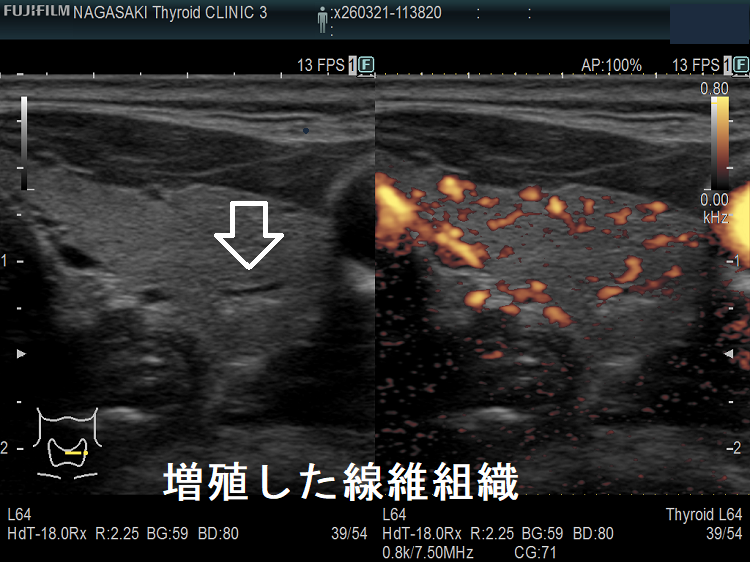

- 甲状腺癌と紛らわしい結節性橋本病(橋本病結節)